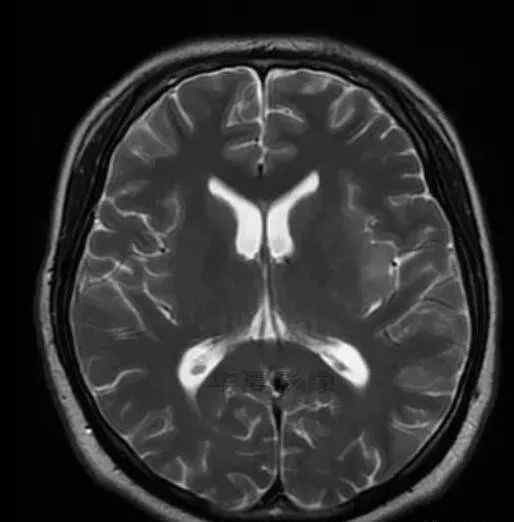

1.左侧颞叶、海马和岛叶T1WI信号低,T2WI信号高

2.病变没有明显的边界

3.占用效果不明显

4.豆状核不受影响